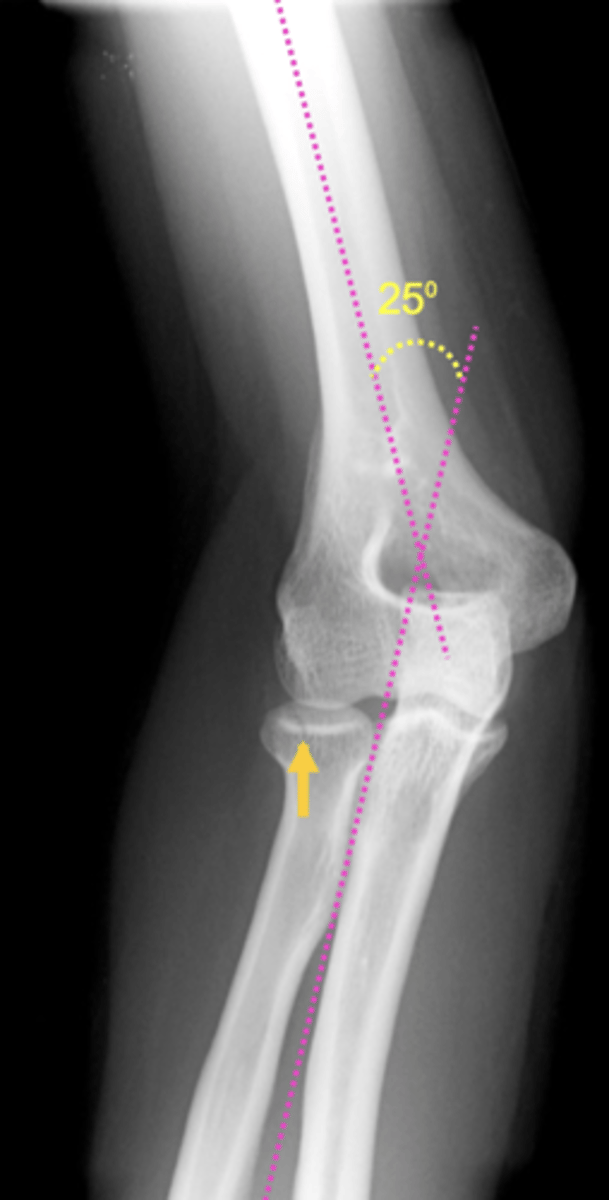

What commonly occurs w/ elbow fractures?

Increased carrying angle (should be 15 degrees)